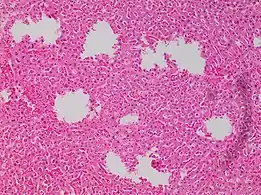

In microscopy, an artifact is an apparent structural detail that is caused by the processing of the specimen and is thus not a legitimate feature of the specimen. In light microscopy, artifacts may be produced by air bubbles trapped under the slide's cover slip.[1]

Air bubble entrapment artifact in a shoulder joint biopsy